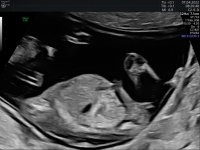

Var visst 13+5 og ikke 13+0 :angelic:. Fint dekorert med navlesnor rundt halsen (som ikke gjør noe). Syns Nub'en ser jentete ut :)

82,3 KB · Visninger: 87

71,6 KB · Visninger: 88